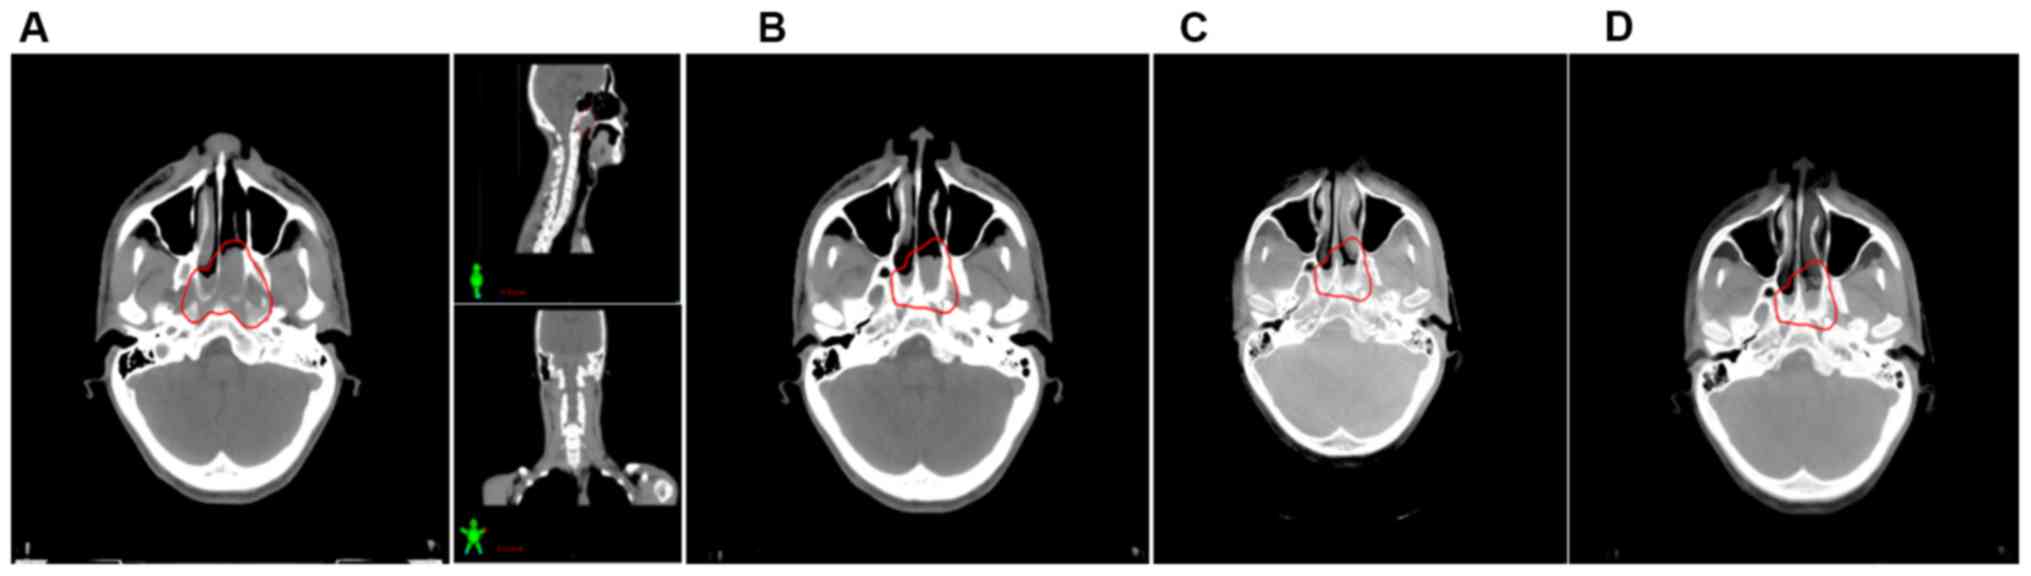

Figure 1.

Image registration in the head region by automatic bone matching and manual fine-tuning. (A) Planning CT images of the cross section, coronal plane and sagittal plane in a patient with NPC; automatic bone matching and manual fine-tuning methods were performed using the nasal septum as a bony landmark. (B) Image of the head in planning CT. (C) Image of the head in cone-beam CT. (D) Typical fusion image of CBCT superimposed with planning CT image. The primary gross volume is outlined in red. CT, computed tomography; NPC, nasopharyngeal carcinoma.